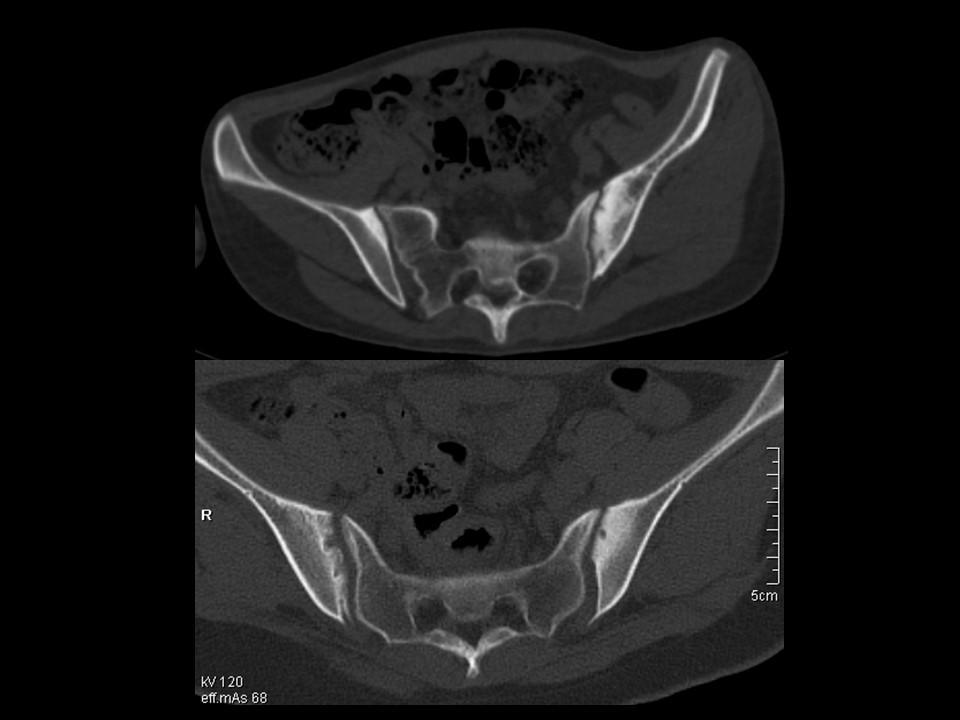

“类风湿性关节炎、强直性脊柱炎影像学诊断PPT” 的相关文章